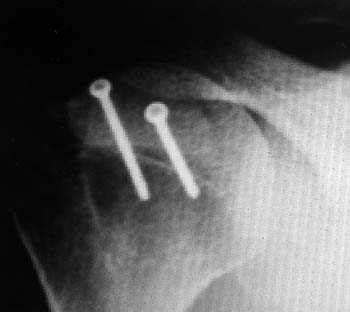

Figura 3: Radiografía de Hombro posterior a Cirugía de Latarjet. A: Radiografía anteroposterior, B: radiografía axial de escápula. Se observan 2 tornillos maleolares.

Lafosse et al.33 plantean realizar este procedimiento en forma completa vía artroscópica, no presentando mayores complicaciones, obteniéndose resultados buenos y excelentes con un seguimiento a corto y mediano plazo (Fig. 3 y 4).